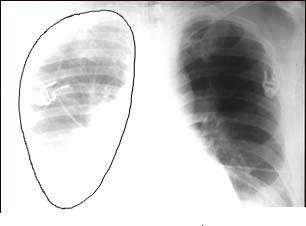

A collapsed lung, or pneumothorax, is the collection of air in the space around the lungs. This buildup of air puts pressure on the lung, so it cannot expand as much as it normally does when you take a breath.

A collapsed lung occurs when air escapes from the lung and fills up the space outside of the lung, inside the chest. It may be caused by a gunshot or knife wound to the chest, rib fracture, or certain medical procedures.

In some cases, a collapsed lung occurs without any cause. This is called a spontaneous pneumothorax. A small area in the lung that is filled with air (bleb) can break open, sending air into the space around the lung.

EXAMS AND TESTS

There are decreased or no breath sounds on the affected side when heard through a stethoscope. You may have low blood pressure.

Tests include: